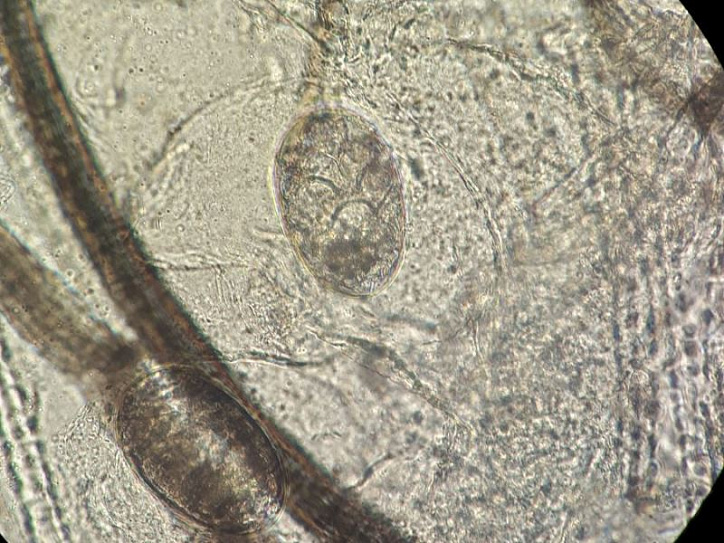

В начале августа к нам в филиал на Свердловском, 18а обратилась молодая пара с маленьким котёнком. При визуальном осмотре стало понятно, что у животного проблемы с шёрстным покровом. На приёме у врача Екатерина (хозяйка котёнка) рассказала, что котика они взяли с рук два дня назад у соседки по саду. Несмотря на поражения у котёнка, которые уже были, молодых людей этот факт не остановил, тем более им сказали, что это не заразно, а так проявляется аллергия на корм. В результате осмотра наблюдались очаги поражения на голове, вблизи ушей. Постоянно почёсывая поражённые места, котик разносил паразитов по всему телу. Вскоре шёрстка начала выпадать, особенно это хорошо было заметно на голове. На голых участках видны коросты. Ко всему прочему, у котика были обнаружены блохи. На приеме животного врачом были взяты анализы крови, соскобы на дерматофитоз (грибковое заболевание) и арахноэнтомоз (паразитарное). При микроскопическом исследовании соскобов с кожи был обнаружен возбудитель паразитарного заболевания – подкожный чесоточный клещ Sarcoptes scabiei, а также споры грибков в и поставлен диагноз – саркоптоз, дерматофитоз, блошиный дерматит.

Возбудители саркоптоза - крошечные паразиты, длина их тельца варьирует от 0,2 до 0,4 мм - питаются эпидермисом, доставляя питомцу дискомфорт и болевые ощущения. Благодаря наличию хоботка клещи прогрызают отверстия в коже и проделывают внутри множество ходов. Они не могут существовать вне тела хозяина размножаться. Одной из главных опасностей патологии считается высокая скорость размножения паразитов. Заметив первые признаки болезни, не стоит откладывать визит к ветеринару.